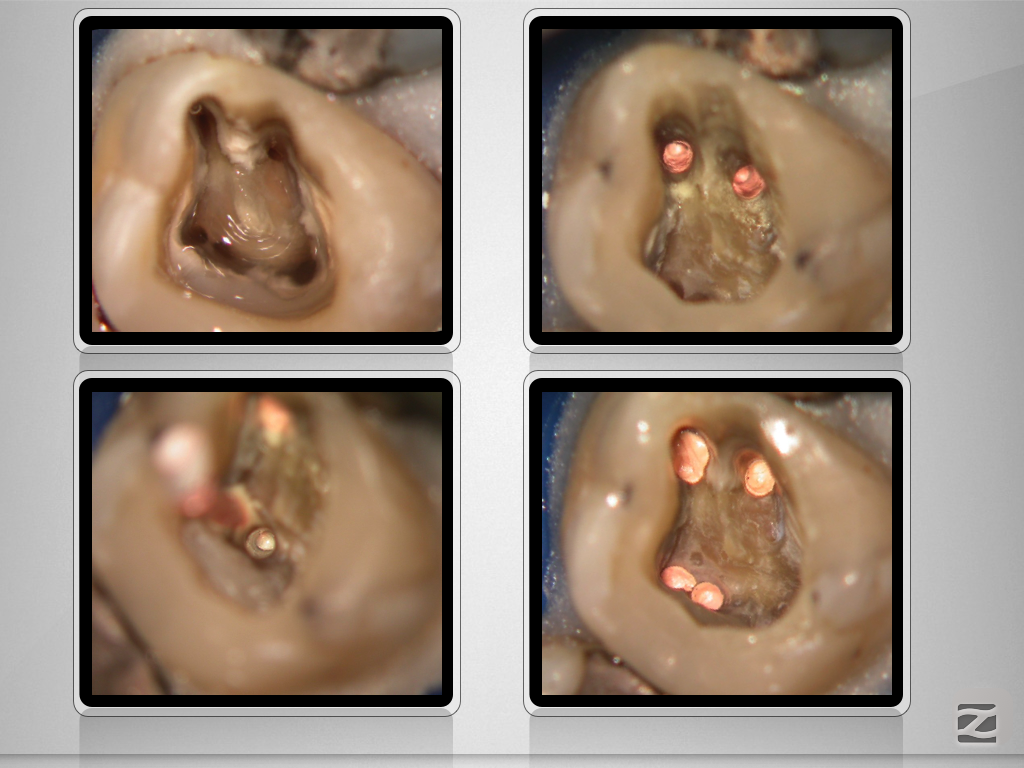

Deutliche Krümmung und kein DVT!